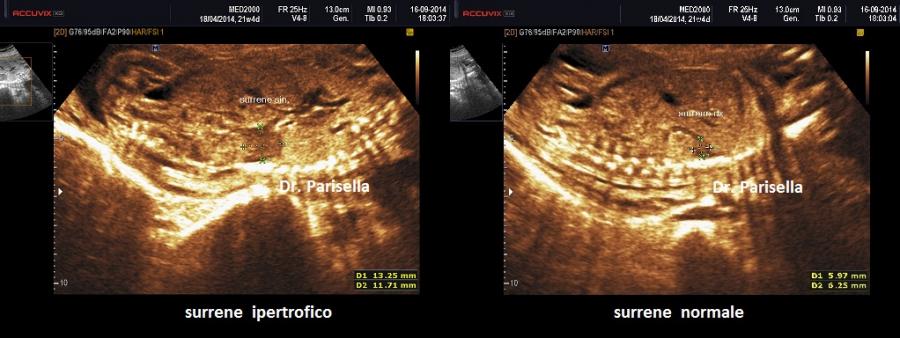

L'ipertrofia surrenalica si può avere in caso di Sindrome adrenogenitale; in tal caso il surrene assume un aspetto rugoso, cerebriforme; questa condizione è associata ad ambiguità genitale nel feto femmina. Alcuni autori hanno proposto  una terapia materna per ridurre la virilizzazione del feto femmina.